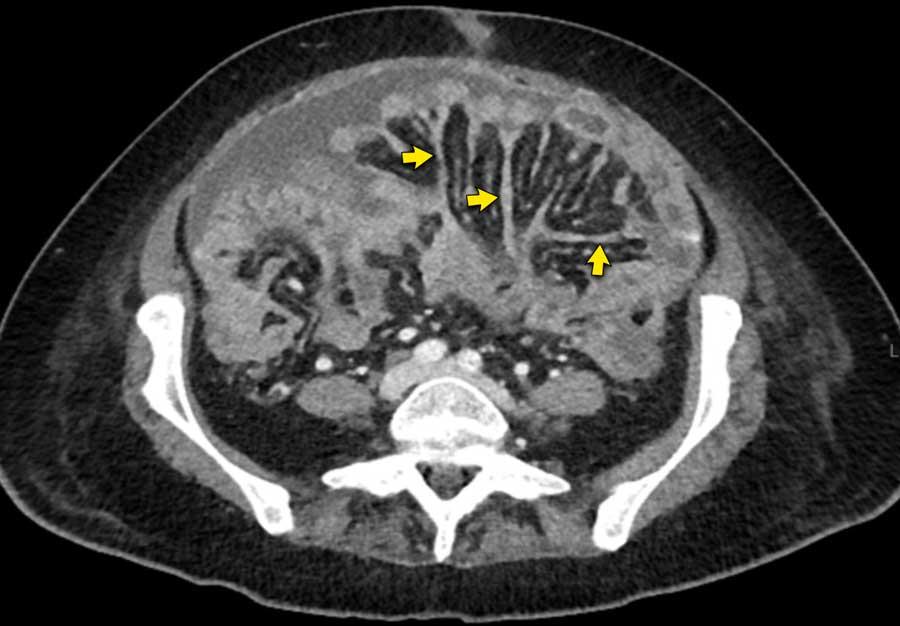

Có một lượng nhỏ dịch cổ trướng.

Mạc treo ruột dày được quan sát thấy bám vào đoạn cuối của ruột non, hình ảnh điển hình của tổn thương xâm lấn mạc treo.

Hình ảnh này thuộc về một bệnh nhân khác nhập viện với cổ trướng.

Hình ảnh

Mạc treo ruột dày (dấu hoa thị) được quan sát thấy bám vào đoạn cuối của ruột non.

Đây là hình ảnh điển hình của tổn thương xâm lấn mạc treo trong ung thư phúc mạc.

Trên CT, hình ảnh dày mạc treo ruột cũng có thể được ghi nhận.